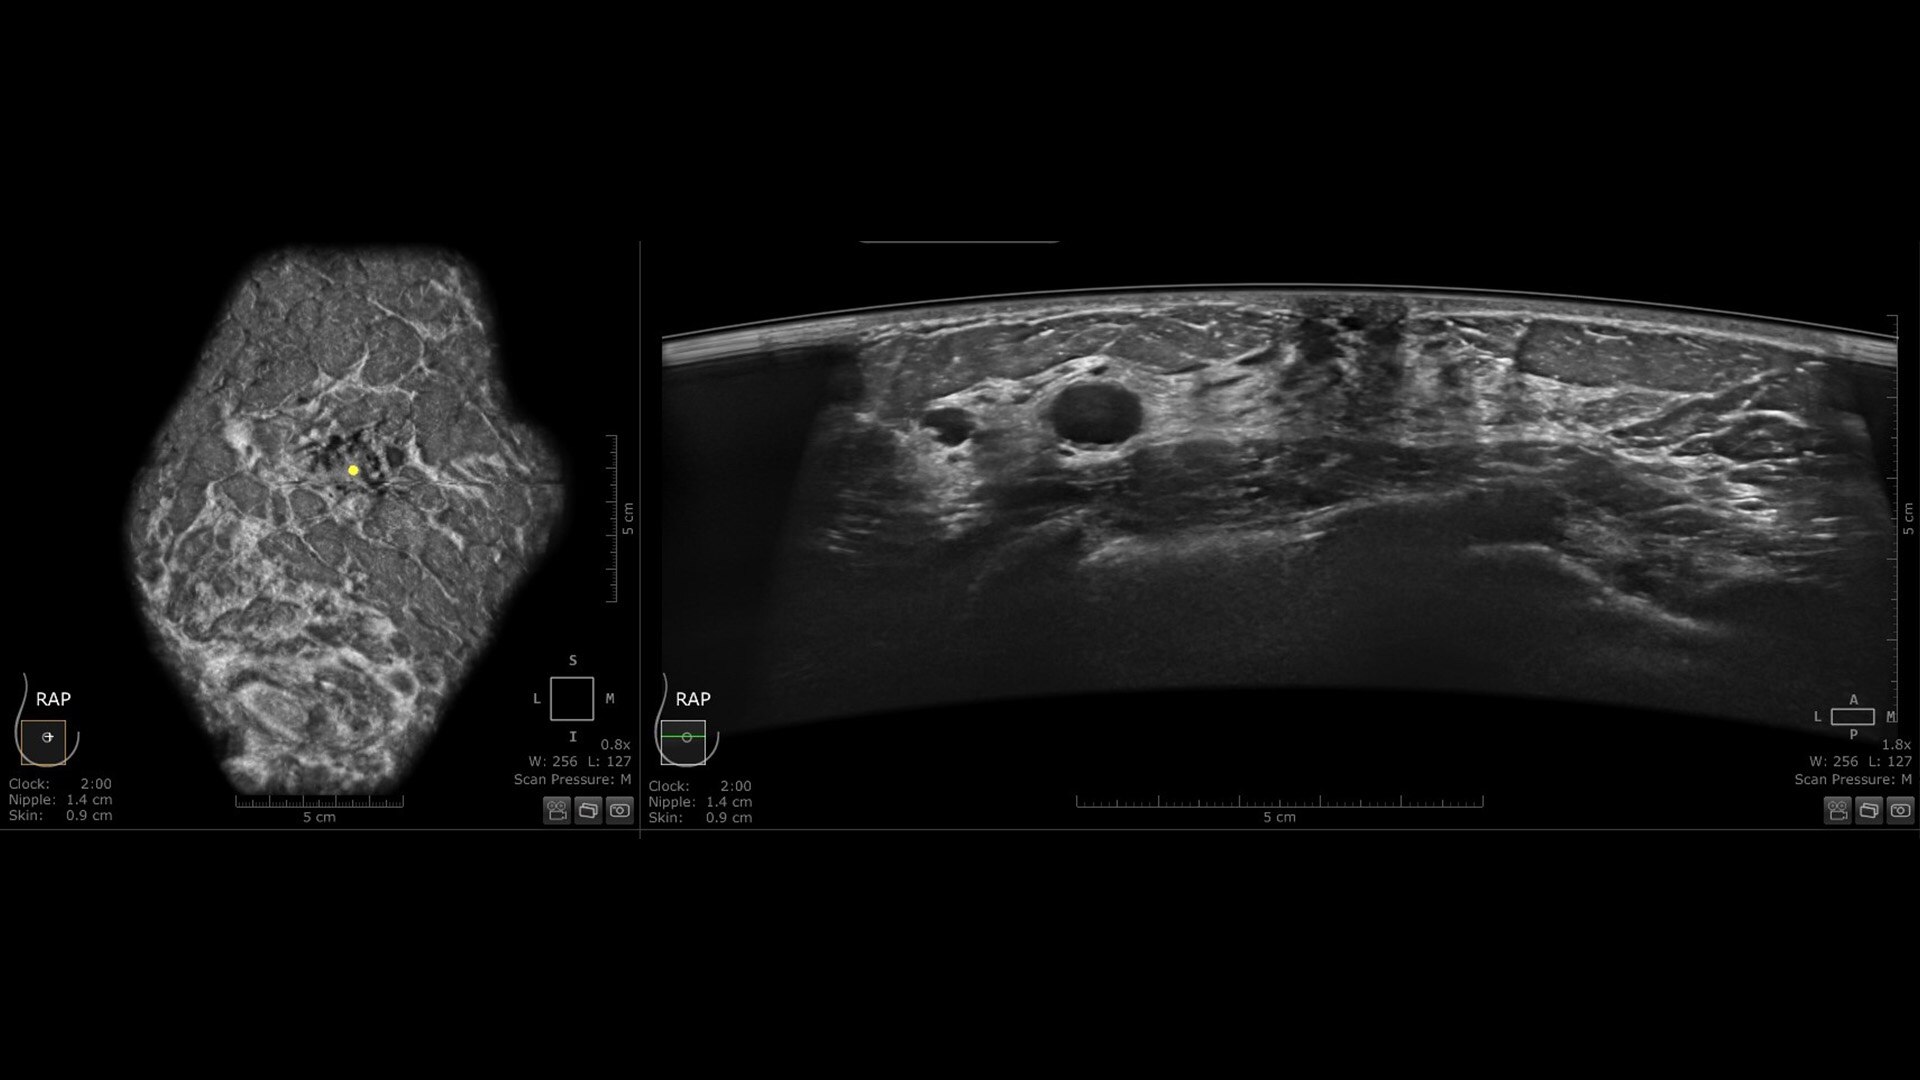

Verisound™ AI-powered solutions enhance confidence and speed workflow

• Scan Quality Assessment provides an immediate, qualitative evaluation for proper breast coverage and positioning.

• Auto Nipple Detection automatically offers nipple marker positioning to enable consistency and speed exams.

The novel Reverse Curve™ transducer is designed for enhanced performance

Its gentle 15.3 cm shape follows the breast's natural contour, enhancing patient comfort* and ensuring full contact for comprehensive coverage. The improved image quality* increases diagnostic confidence for reading ABUS exams.

Excellent image quality and 40% faster scan speed

• cSound Imageformer, software-based processing, produces exquisite, reproducible images by leveraging automatic focus at every pixel.

• Fast Scan increases scan speed by 40%*, fostering improved efficiency and patient throughput.